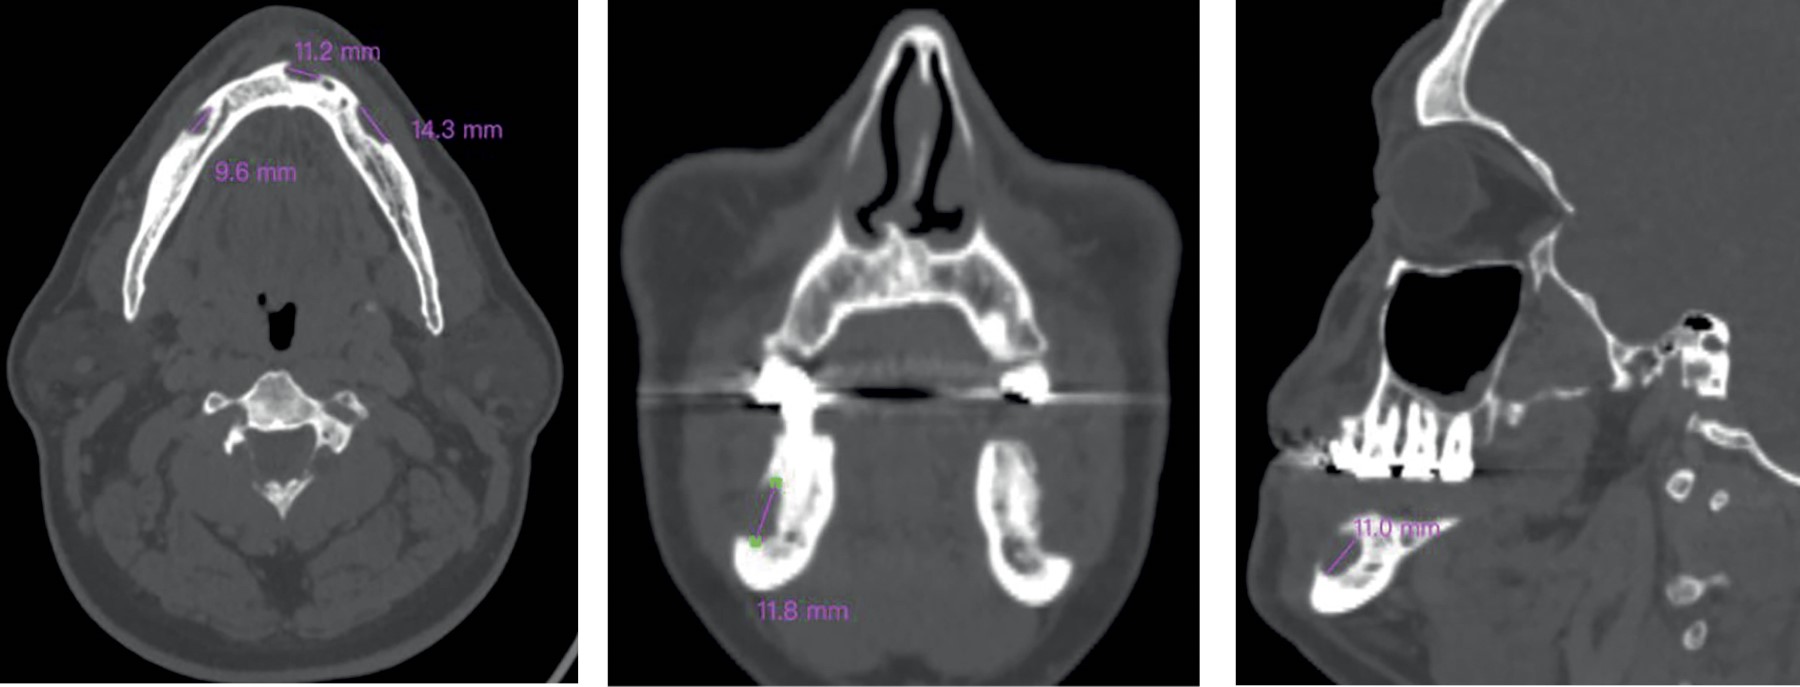

Sin presentar mejoría de sintomatología dolorosa y con exacerbación de ésta a 6/10 en EVA, se realiza estudio imagenológico de tomografía de macizo facial en fase simple con cortes finos de 0.6 mm con fecha 11/Marzo/2023. En el corte axial, sagital y coronal, se observan lesiones osteolíticas en cuerpo mandibular bilateral, con bordes mal definidos (Figura 3).

Figura 3